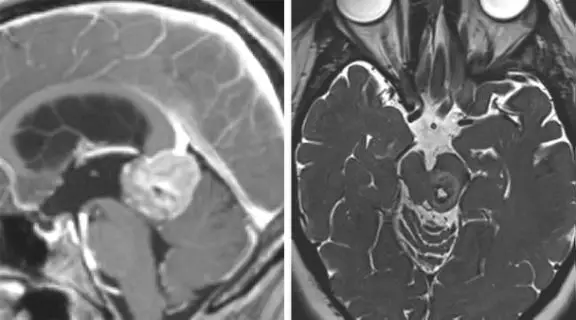

图2. 松果体区(左图)及中脑后外侧(右图)大型病变可以很容易通过小脑上入路显露。